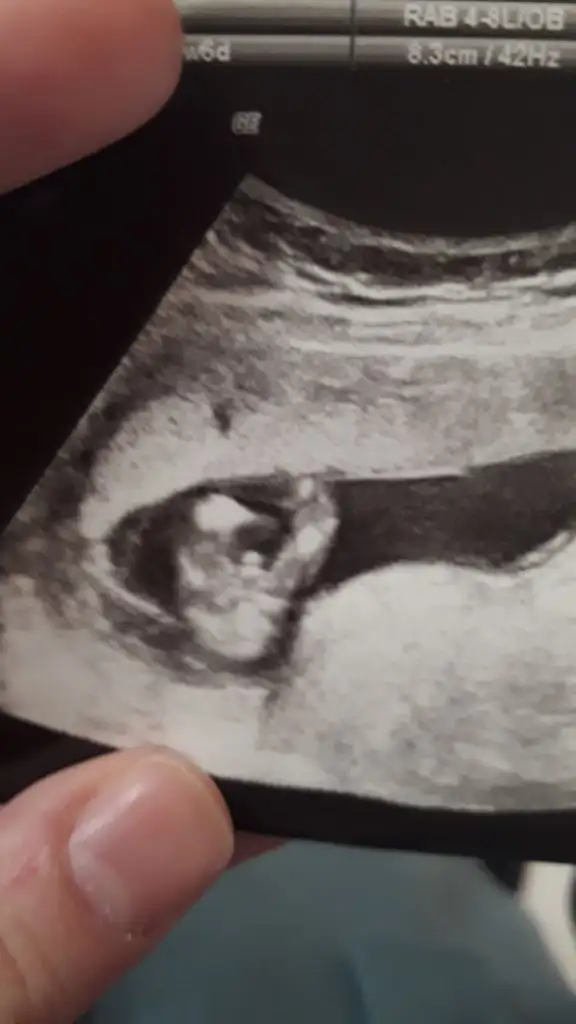

Arkadaşlar hamiş olan anne adaylarımıza hayırlı bir hamilelik dilerim. Bende 5 hafta 6 günlük hamileyim ilk kontrolüm gitmiş bulunmaktayım.Doktorum erkek bebek kesesine benziyor tabi hazırlık yapmayın sakın ha dedi. Bende konuyu araştırırken bu teoriye denk geldim yorumlarmısınız acaba.

ne demekmiş erkek bebek kesesi? Sordunuz mu nerden anladınız diye? Yuvarlak olması mı?